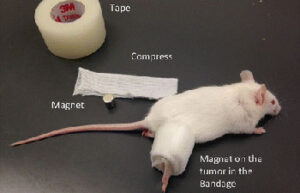

- Maintenance and replacement of mice and rat bandages